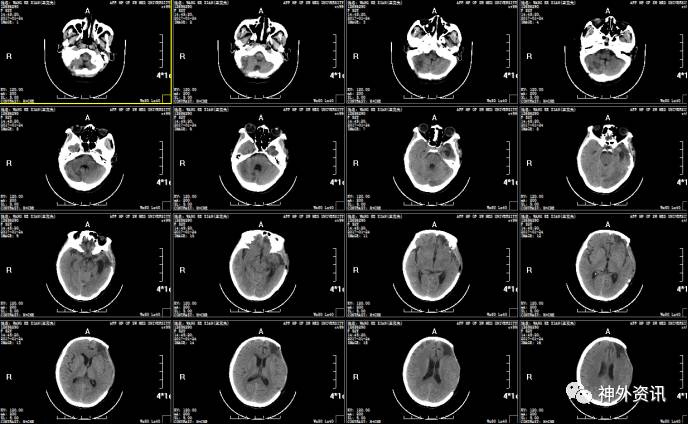

2016.12.24:患者意识仍昏迷,双瞳等大形圆直径约2.0mm,光反射迟钝,复查头颅CT发现脑室系统积血存在,三脑室及侧脑室明显扩大,考虑脑室积水,在急诊局麻下行:右侧脑室外引流术,考虑患者短时间内不能清醒,予以气管切开处理。

2016.12.25:侧脑室外引流术后第1天复查头颅CT,脑室系统积血明显减少,脑室大小恢复。继续予以脱水、促醒、预防感染等对症支持治疗,血浆引流管爬坡10cm,密切观察患者病情变化。

箭头为脑室引流管